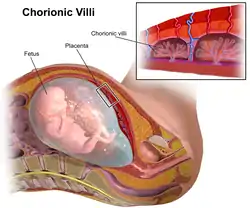

Chorionic villi are villi that sprout from the chorion to provide maximal contact area with maternal blood.

They are an essential element in pregnancy from a histomorphologic perspective, and are, by definition, a product of conception. Branches of the umbilical arteries carry embryonic blood to the villi. After circulating through the capillaries of the villi, blood returns to the embryo through the umbilical vein. Thus, villi are part of the border between maternal and fetal blood during pregnancy.

The chorion undergoes rapid proliferation and forms numerous processes, the chorionic villi, which invade and destroy the uterine decidua and at the same time absorb from it nutritive materials for the growth of the embryo. They undergo several stages, depending on their composition.